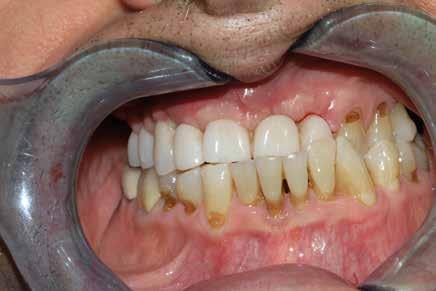

La proposta che il paziente ha accettato è stata poi quella, previa bonifica di tutti gli elementi irrecuperabili, di riabilitare con impianti prima il 1° e 4° quadrante e in seguito il 2° e 3° e procedere poi alla protesi definitiva in un’unica soluzione.

riferico. Si è eseguito la maggior parte delle estrazioni in un’unica seduta operatoria, a esclusione degli elementi 2.6 e 4.7 che sono stati mantenuti perché presentavano mobilità ma non segni di focolai infettivi attivi e che si è deciso di estrarre in un secondo momento. Il follow-up post estrattivo ha consentito anche di valutare la risposta tissutale e la guarigione degli alveoli. Non è stata sospesa la terapia con l’acido acetilsalicilico. Il PRGF è stato importante per evitare alveoliti che avrebbero rallentato la guarigione (Figg. 4-6).

Dopo tre mesi dalla prima fase estrattiva sono stati ripetuti gli esami ematochimici dai quali l’emoglobina glicata del paziente è scesa a 7.2%. Abbiamo pertanto avviato con lo studio pre-implantare che prevede la ceratura diagnostica e gli esami radiologici più avanzati per scegliere i giusti impianti e la loro sede corretta.

L’esame CBCT ha rivelato un quantitativo di osseo sufficiente a procedere con l’intervento implantare, anche se erano ancora visibili le zone delle estrazioni; inoltre ha evidenziato una lesione osteolitica a carico del 3.5 che abbiamo dunque deciso di estrarre (Figg. 7-20).